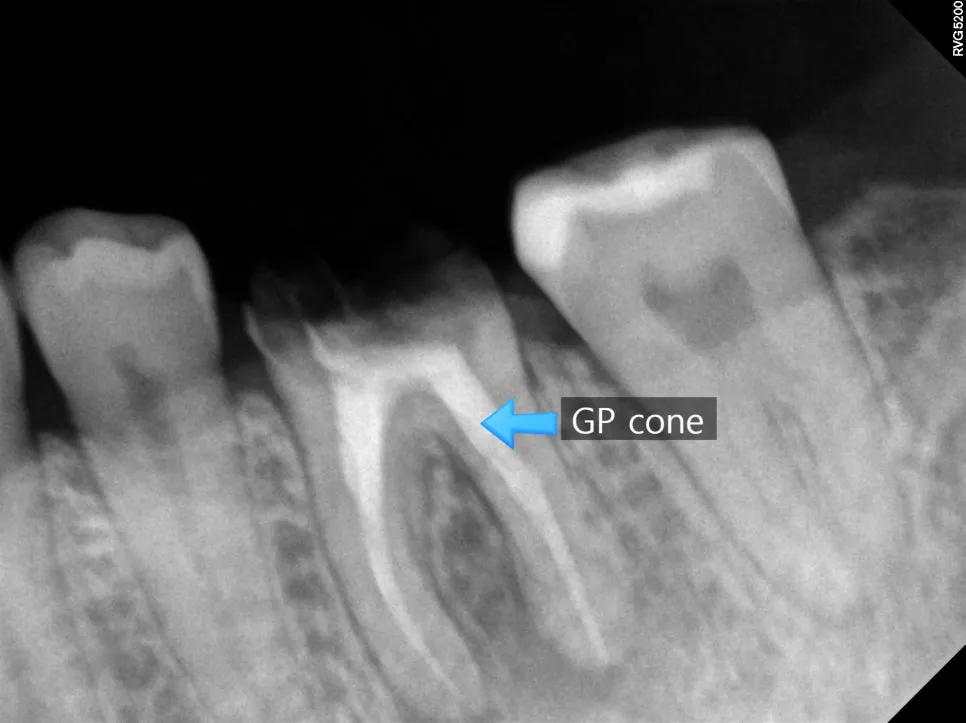

기존의 단단한 충전재(GP cone)를 제거하고, 신경관 길이를 다시 측정하여 뿌리 끝까지 기구가 도달하도록 합니다. 이 과정에서 놓치는 신경관이 없어야 성공률이 높아집니다.